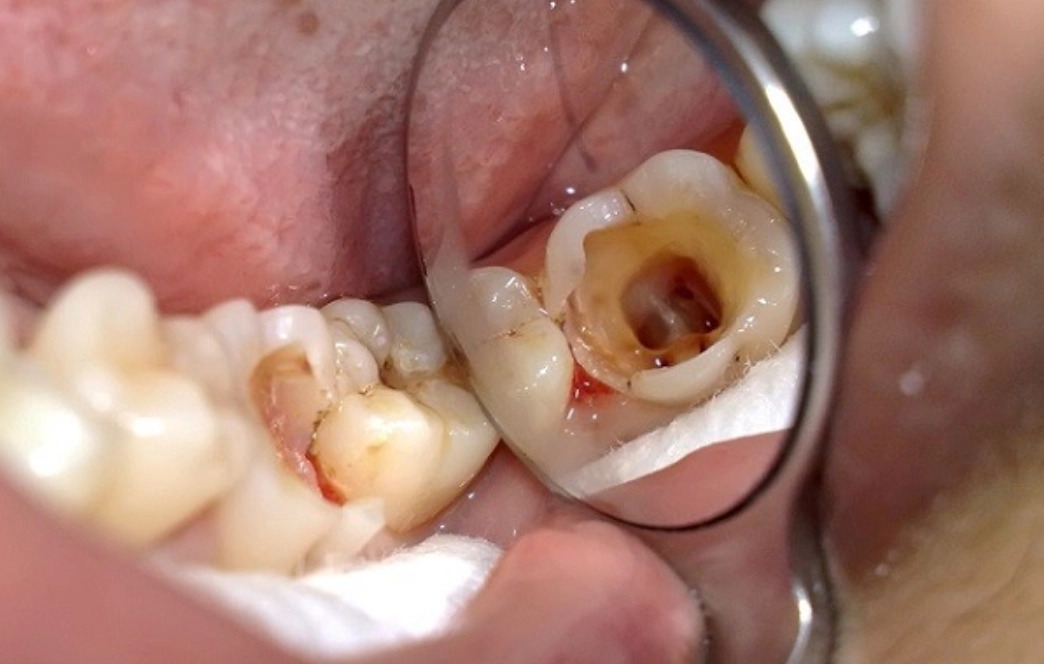

3.1. Dấu hiệu cho thấy tủy răng đang “kêu cứu”:

- Răng vỡ lớn do sâu hoặc chấn thương làm lộ tủy

3.2. Lý do bạn cần điều trị tủy răng là gì?

- Loại bỏ ổ nhiễm trùng: Làm sạch vi khuẩn và mô hoại tử trong ống tủy, ngăn viêm nhiễm lan rộng

- Tránh biến chứng nguy hiểm: Viêm tủy không điều trị có thể gây áp xe, viêm xương hàm, nang chân răng, thậm chí nhiễm trùng máu

- Thăm khám, chẩn đoán chính xác: Bác sĩ thăm khám kỹ lưỡng, chụp X-quang hoặc CT Cone Beam để xác định tình trạng tủy răng và lên kế hoạch điều trị chi tiết.

- Trải nghiệm nhẹ nhàng: Kỹ thuật gây tê hiện đại và công nghệ nội nha tiên tiến (máy nội nha quay, định vị chóp) giúp quá trình điều trị chính xác, hiệu quả và không đau.

- Trám bít ống tủy và phục hồi răng: Sau khi làm sạch, ống tủy được trám bít kín bằng vật liệu chuyên dụng. Bọc răng sứ là giải pháp tối ưu để bảo vệ răng khỏi nứt vỡ và khôi phục chức năng, thẩm mỹ.